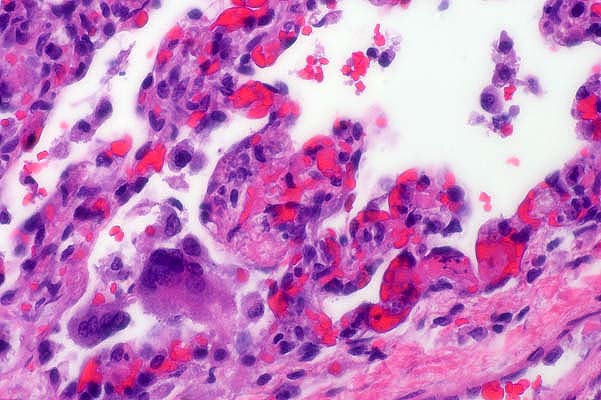

- Contributor's Diagnosis and Comments: Lung: Severe

diffuse subacute interstitial pneumonia with intralesional yeasts

(Candida lusitaniae).

- Organisms were also found in the thymus, spleen, and liver.

Additionally there was evidence of erythrophagocytosis in the

spleen as well as disseminated intravascular coagulopathy. Systemic

- Case 28-4. Occasional foreign body giant cells, macrophages

and cell debris within alveoli and alveolar septa. Scattered

macrophages contain multiple 3-4um basophilic organisms.

- AFIP Diagnoses:

- 1. Lung: Pneumonia, interstitial, granulomatous, diffuse,

severe, with numerous intrahistiocytic yeasts, thoroughbred,

equine.

2. Lung, blood vessels: Fibrin thrombi, with yeasts.

- Conference Note: Conference participants considered

a broad differential diagnosis that included Histoplasma capsulatum,

Cryptococcus neoformans, Blastomycetes dermatitidis, Sporothrix

schenckii, Coccidioides immitis, Leishmania sp., Toxoplasma gondii,

and Neospora caninum. Candida spp. can be identified in tissue

when yeasts, hyphae and pseudohyphae are all present. In cases

where all three structures are not present, culture is required

for definitive diagnosis. Yeasts, hyphae and pseudohyphae are

clearly evident in sections stained with GMS and PAS.

- Along with pneumonia, systemic candidiasis may cause synovitis,

panophthalmitis, meningitis, glossitis, osteomyelitis and cystitis.